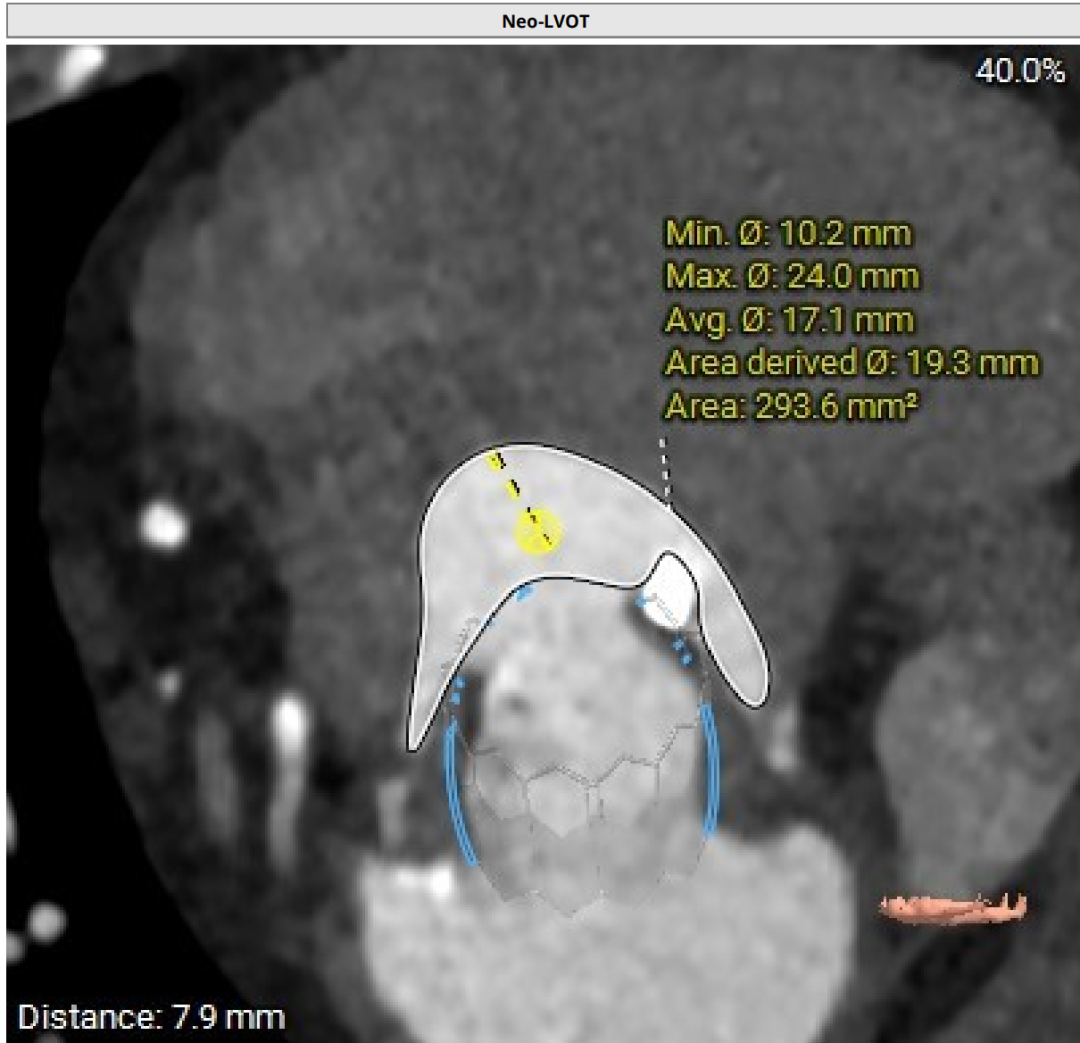

NEO-LVOT面积293.6mm²,新流出道梗阻风险低

谷兴华教授团队组织经过多学科讨论,认为:因患者71岁,基于全生命周期管理的理念,需要选用较大尺寸、更大EOA的介入瓣膜,以备第二次MVIV。最终的手术方案为:经心尖入路,先用25#Renatus标准压力释放,再用24mm的Atlas Gold球囊高压后扩,将25#原人工Mosaic生物瓣环扩断。